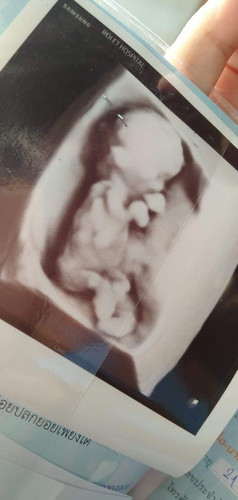

ยาที่คุณหมอให้มาตัวเป็นกระปุกบ้านนี้ทานไปแล้วคุณแม่เกิดอาการวินเวียนแล้วก็อาเจียนออกมาค่ะแล้วก็กินนมไม่ค่อยได้เพราะว่าส่วนตัวเป็นคนแพ้นมถั่วเหลืองอยู่แล้วแล้วกินนมวัวช่วงนี้กินเข้าไปก็คืออ้วกตั้งแต่เริ่มรู้ตัวว่าท้องจะถึงตอนนี้ตอนนี้อายุครรภ์ก็ประมาณ 14 สัปดาห์แล้วค่ะยังไม่หายแพ้เลยควรทำยังไงดีคะ ปล.รูปด้านล่างเป็นรูปลูกนะคะอยากทราบว่าแบบนี้ปกติดีไหมเพราะท้องแรกเราไม่เคยมีลูกมาก่อนอยากรู้ว่าลูกสมบูรณ์ดีไหมคะเป็นแบบนี้